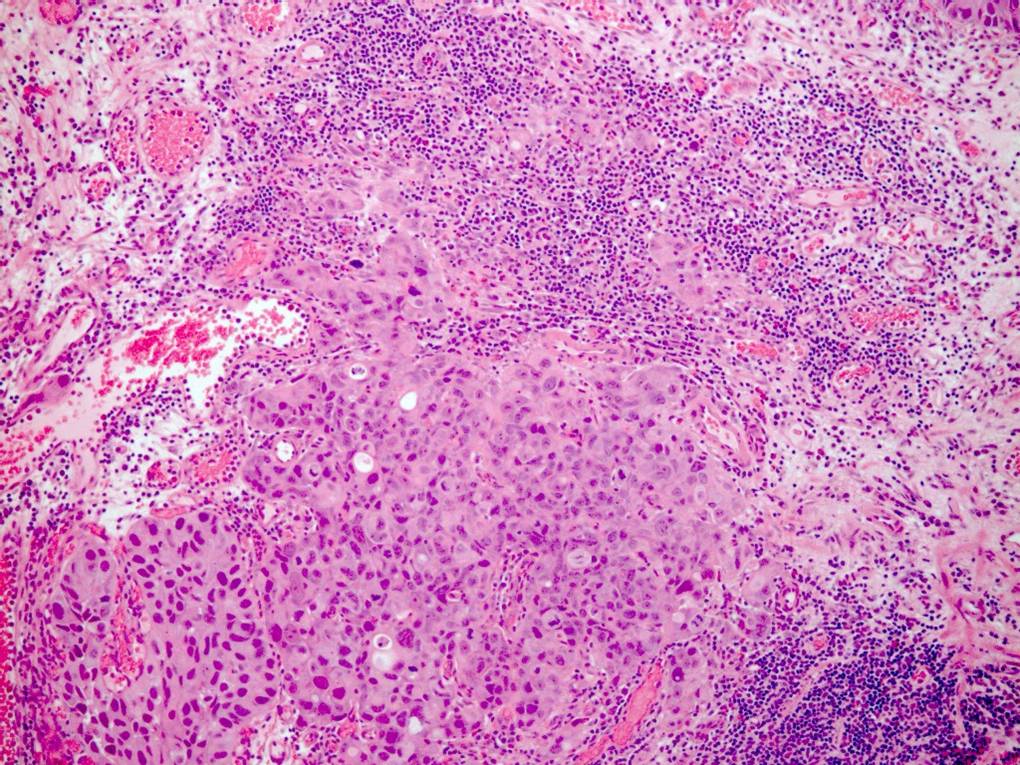

Consensus grade: High-grade papillary urothelial carcinoma (HG-PUC)

Case description (by case creator):

61 year old male. History of haematuria. Diagnosis = high grade papillary urothelial carcinoma with lamina propria invasion.